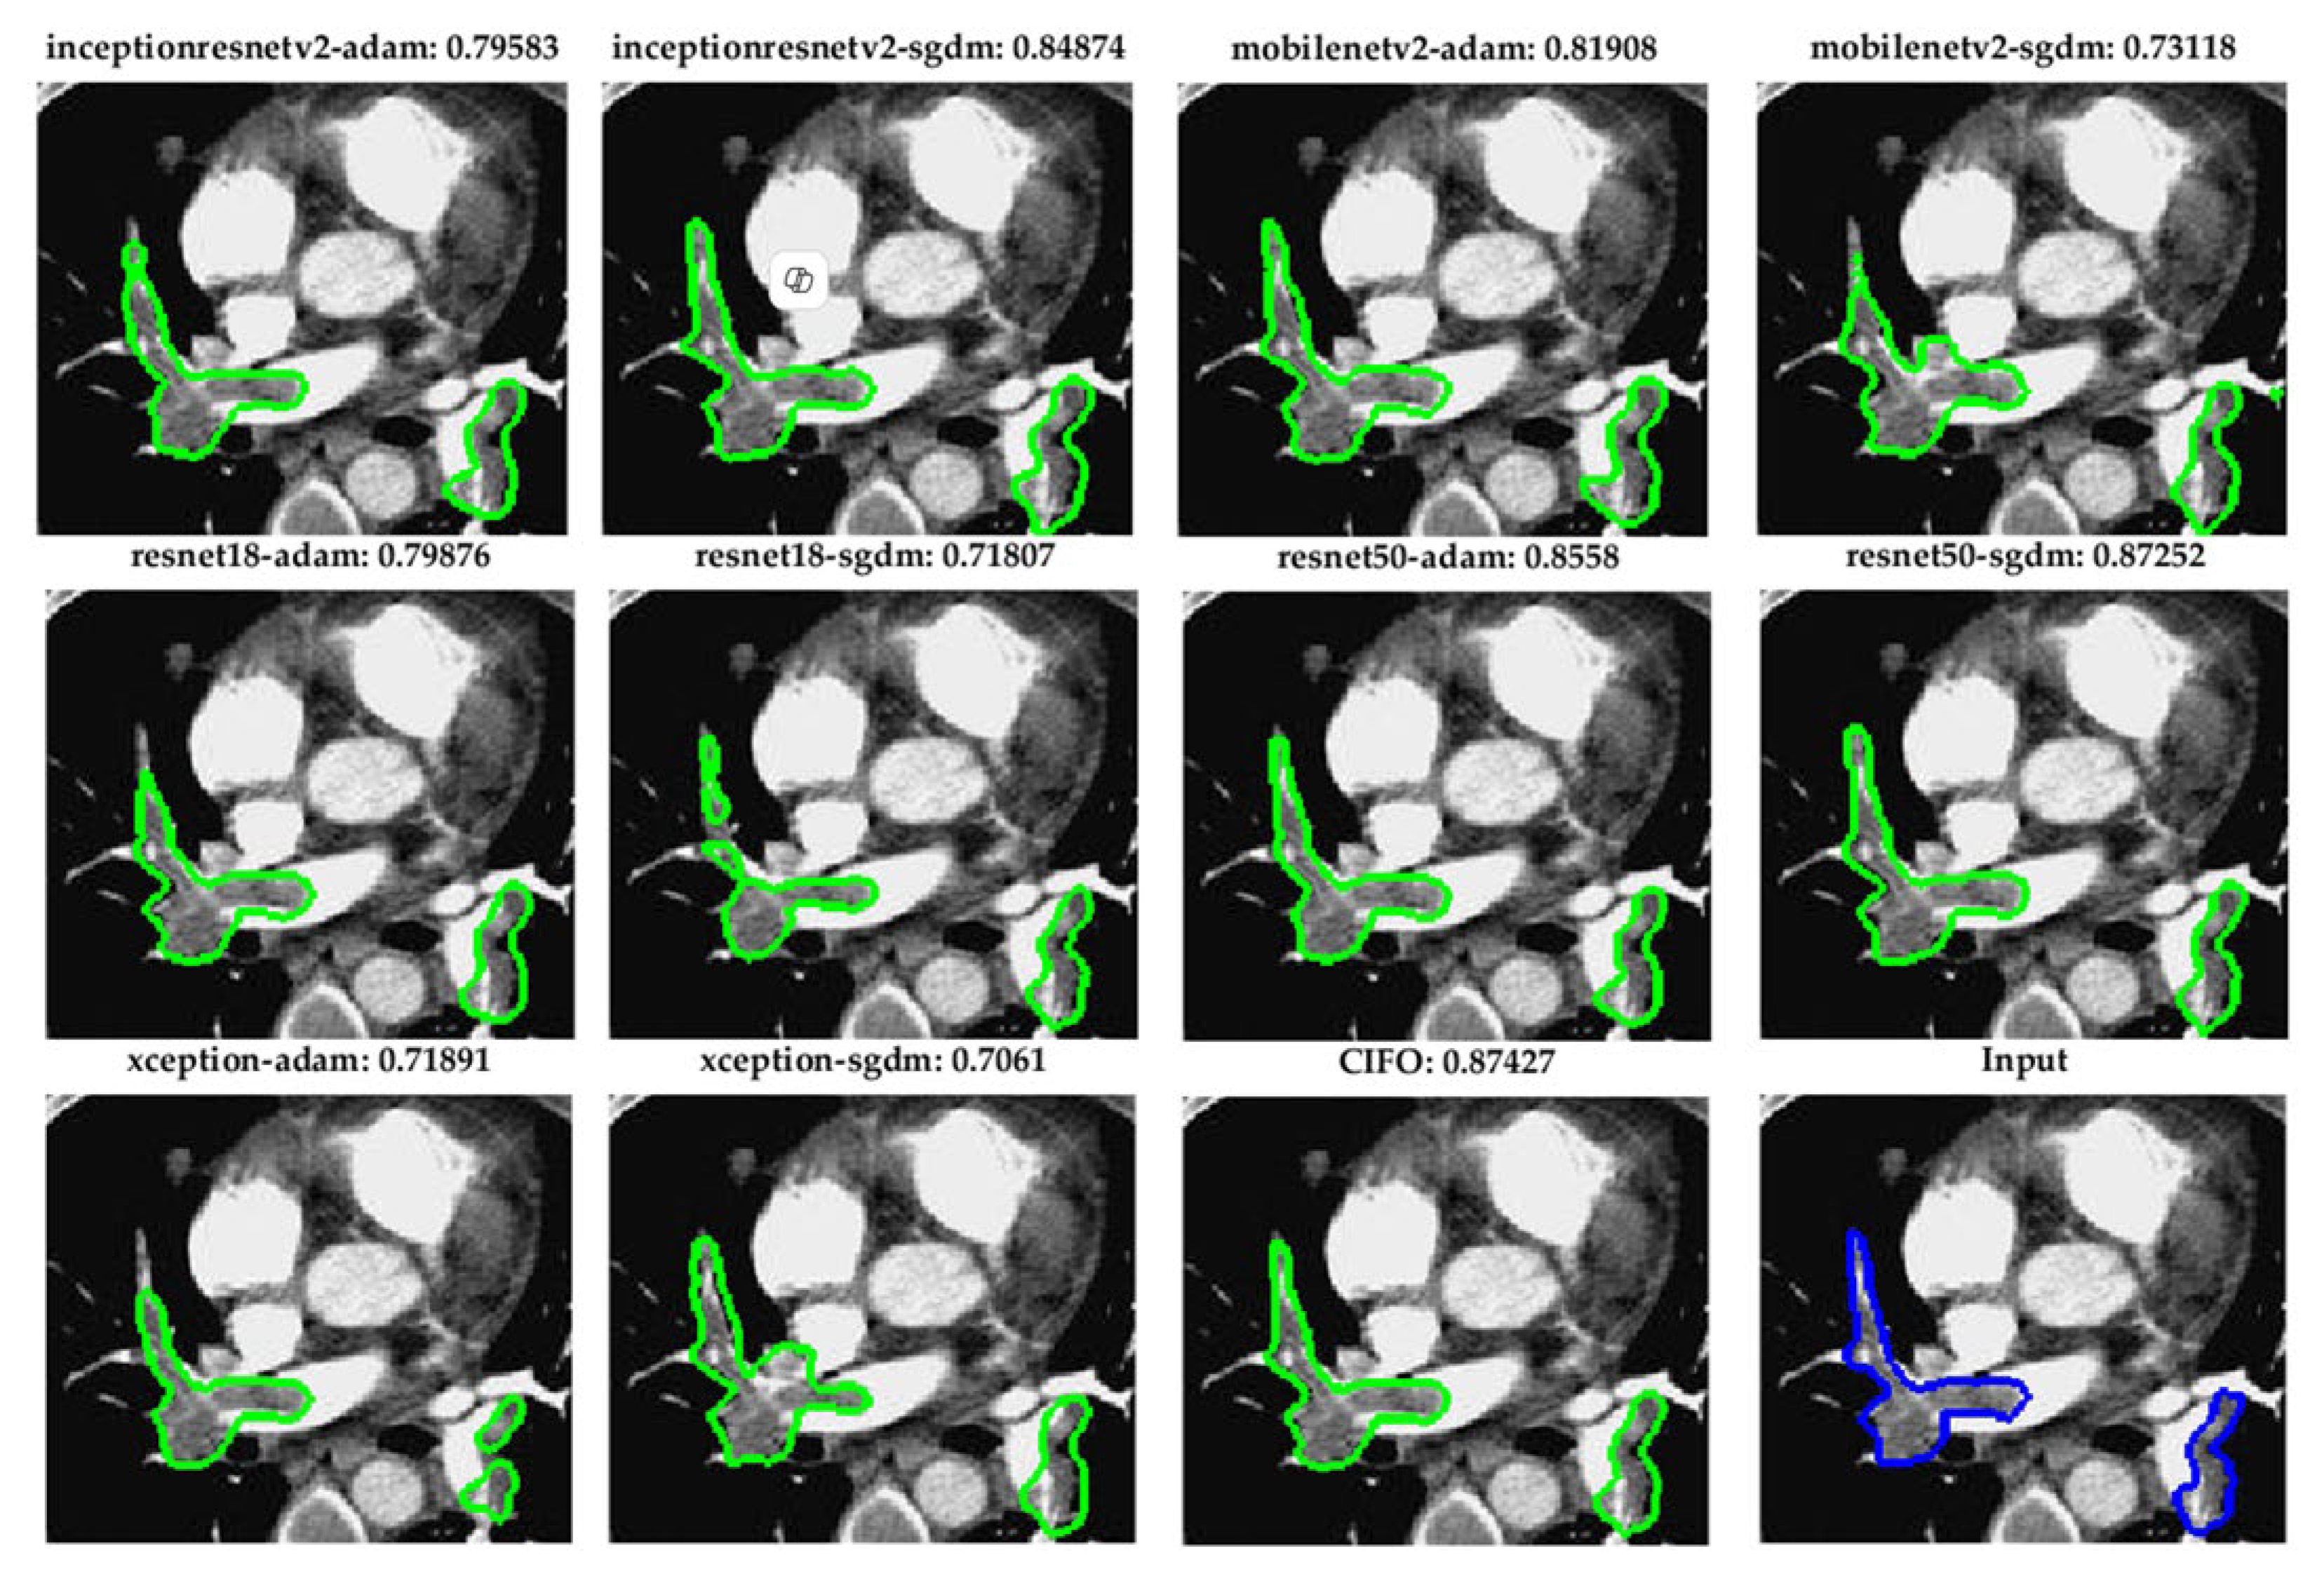

Figure 5. Visual comparison of pulmonary embolism (PE) segmentation results using ten fully convolutional network (FCN) models and the proposed CIOF fusion method. Each subfigure displays the segmented result (green contour) overlaid on a CT angiography slice, with the Dice coefficient shown above each result. The CIOF method demonstrates superior performance (Dice: 0.87427) compared to individual models. The original image and ground truth annotation (blue contour) are shown in the bottom-right panel for reference.

5.2. Robust Segmentation of Subsegmental Emboli with CIOF Fusion

Figure 6 demonstrates segmentation outcomes of small pulmonary emboli (<26 pixels) across ten fully convolutional network (FCN) configurations and the CIOF ensemble method. Each sub-image includes the original CTA slice with overlaid segmentation results. The Dice similarity score is displayed above each panel. The CIOF method demonstrates superior performance (Dice: 0.91045) compared to individual models. CIOF consistently provides a more accurate and complete delineation of emboli compared to individual models, especially in challenging small-vessel regions.